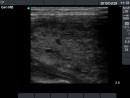

Follow-up examinations (rows from 1st to 8th):

2. Note the relation between volume, echogenicity, vascularization and hormone levels.